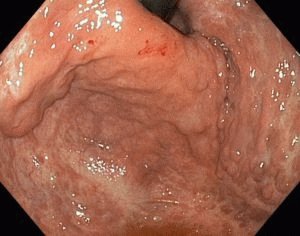

Лечение эрозивного гастрита

При подозрении на эрозивный гастрит больной проходит комплексное обследование, которое включает проведение лабораторного исследования крови и мочи, осмотр слизистой желудка с помощью фиброгастродуоденоскопии (ФГДС) и обследование органов брюшной полости на УЗИ. Только после постановки диагноза и определения вида гастрита может быть назначено адекватное лечение.

На восстановление слизистого слоя требуется много времени, поэтому терапия длительная

Диагноз должен быть подтвержден ФГДС, поскольку гастрит мало чем отличается от язвенной болезни. Лечение гастрита и язвы желудка должно быть направлено на устранение провоцирующего фактора и предотвращение его появления в дальнейшем. Чтобы быстро устранить болевой синдром и предотвратить возникновение язвы назначается медикаментозная терапия.

При обширных поражениях слизистой и обильном кровотечении показана коагуляция. Во время процедуры эрозии прижигаются специальным лазером. Проводится это при помощи эндоскопа. Если эрозии продолжают кровоточить, то необходимо удаление пораженного участка слизистой.